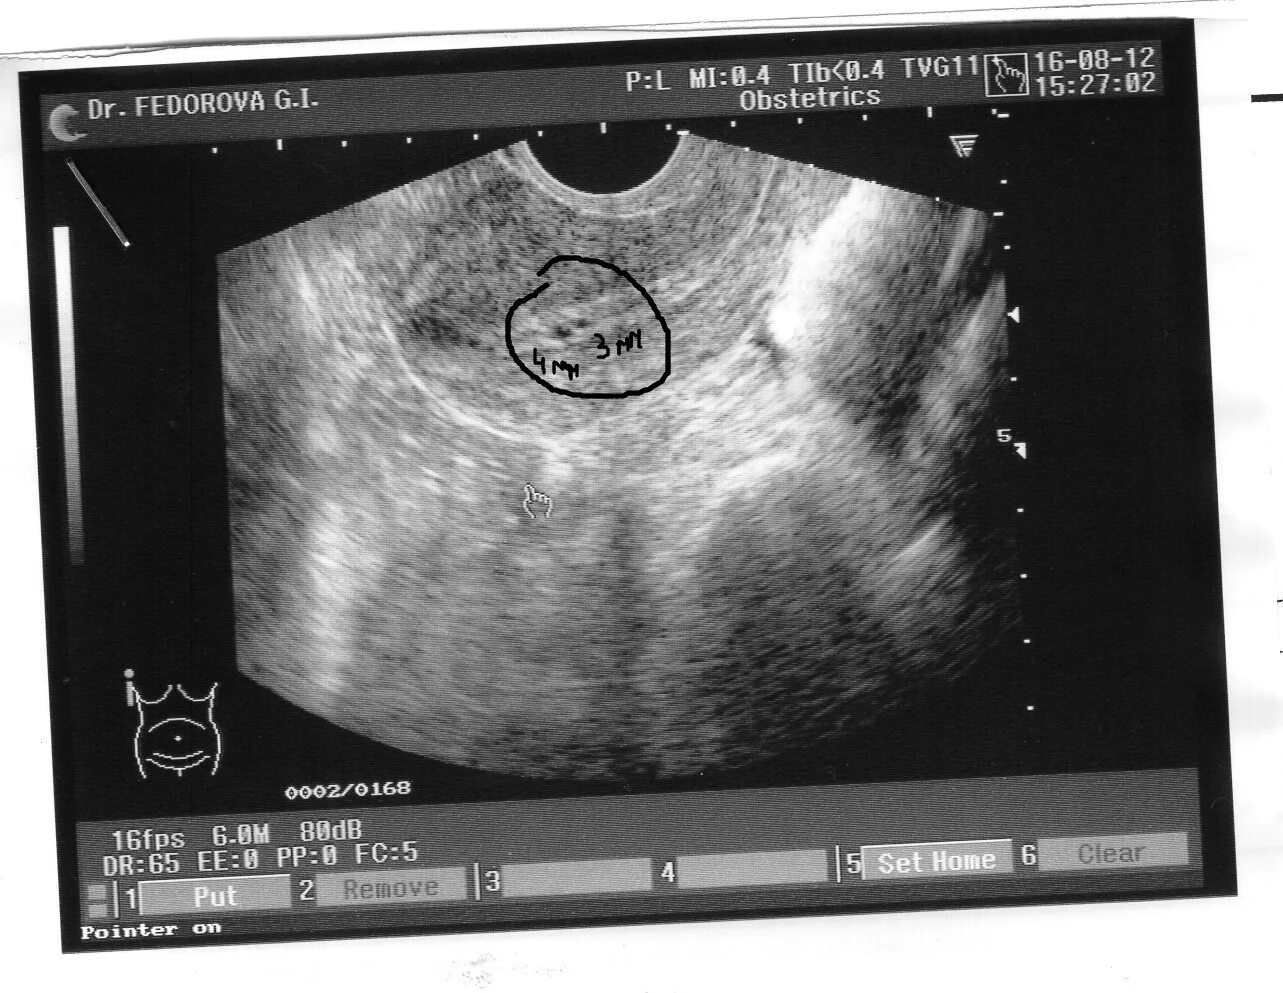

Акушерский срок